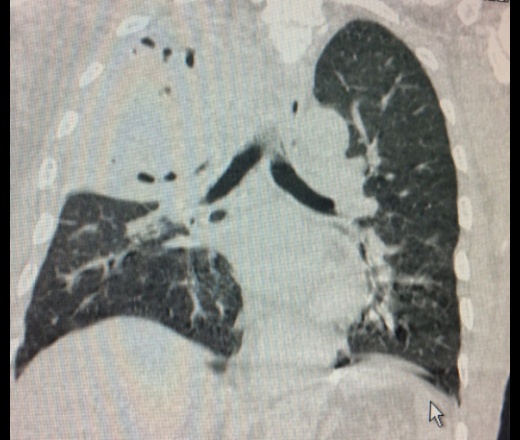

Понимание бактериальной пневмонии через снимки